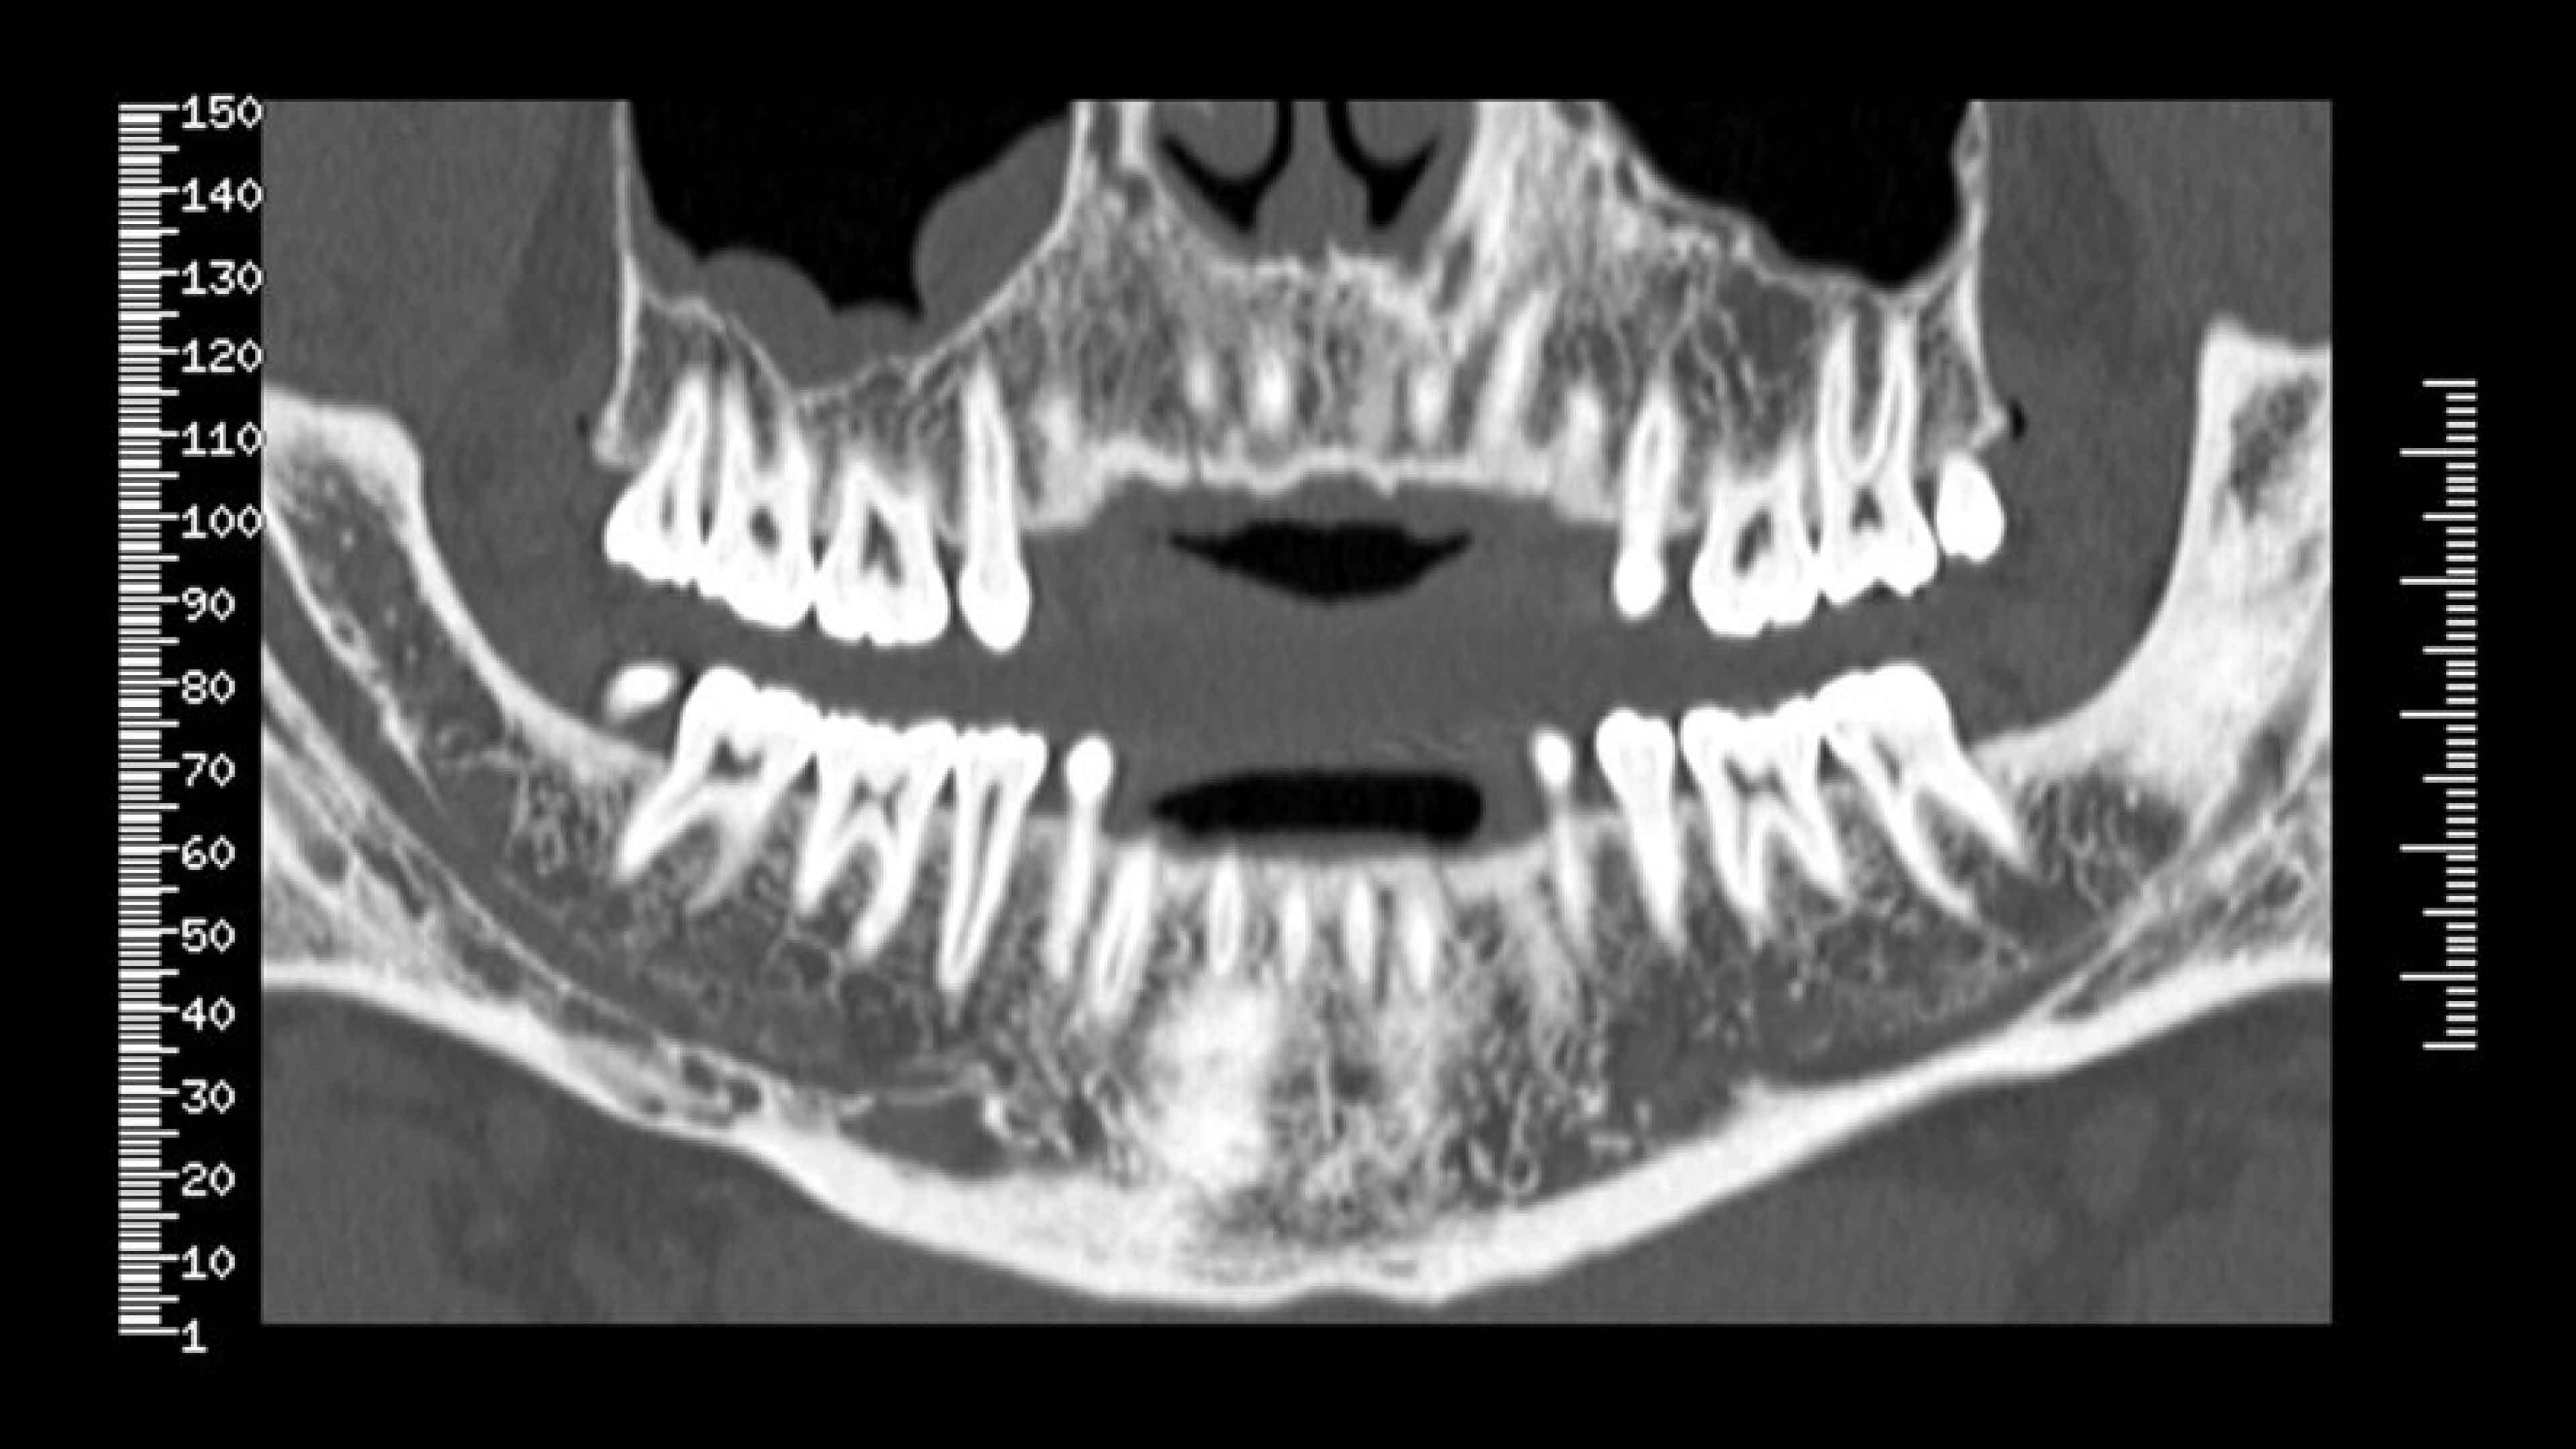

Panorex and oblique views

Cross-referenced views

Axial, panorex and oblique views remain cross referenced on the screen.

• Axial panorex and oblique views remain cross referenced on the screen. Oblique views are generated in real time when the cursor is moved on axial or panorex views. A similar feature exists when the cursor is moved on a panorex or oblique view.

• A mm-scale is printed on the side of oblique and panorex views for direct measurement from film. The entire study is annotated to assist in film interpretation.